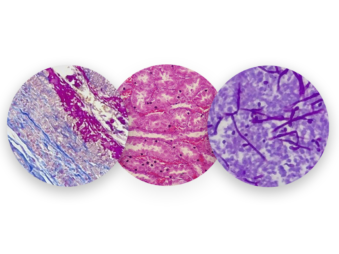

Nuestros Estudios

En H&E Diagnostics contamos con tecnología de última generación y personal altamente capacitado para el diagnóstico y entrega oportuna de resultados ofreciendo los siguientes servicios especializados: